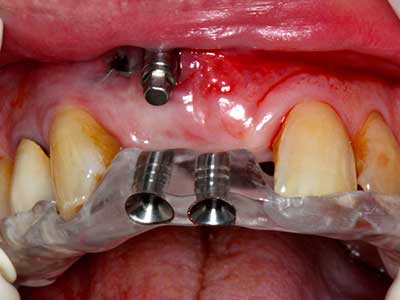

Indication: Preparation near nerves

Indication: Apical resection

When surgical procedures are performed on bone in the immediate vicinity of sensitive structures such as blood vessels or nerves, rotary instruments pose a significant risk of iatrogenic injury. Piezoelectric devices can be helpful for preparation of bone covers and removal of hard tissue close to nerves, particularly for exposure of nerves after iatrogenic injury but also during nerve lateralization for resective and reconstructive procedures or implant placement (Fig. 17-20). Light contact between the piezotip and the nerve does not generally result in damage but proceeding incautiously with saw-like motions or attachments where a residual bone substrate remains may cause temporary or even permanent nerve damage. However, the risk of damage is considered to be substantially lower than when using saws or milling instruments (Pereira, Gealh et al. 2014).